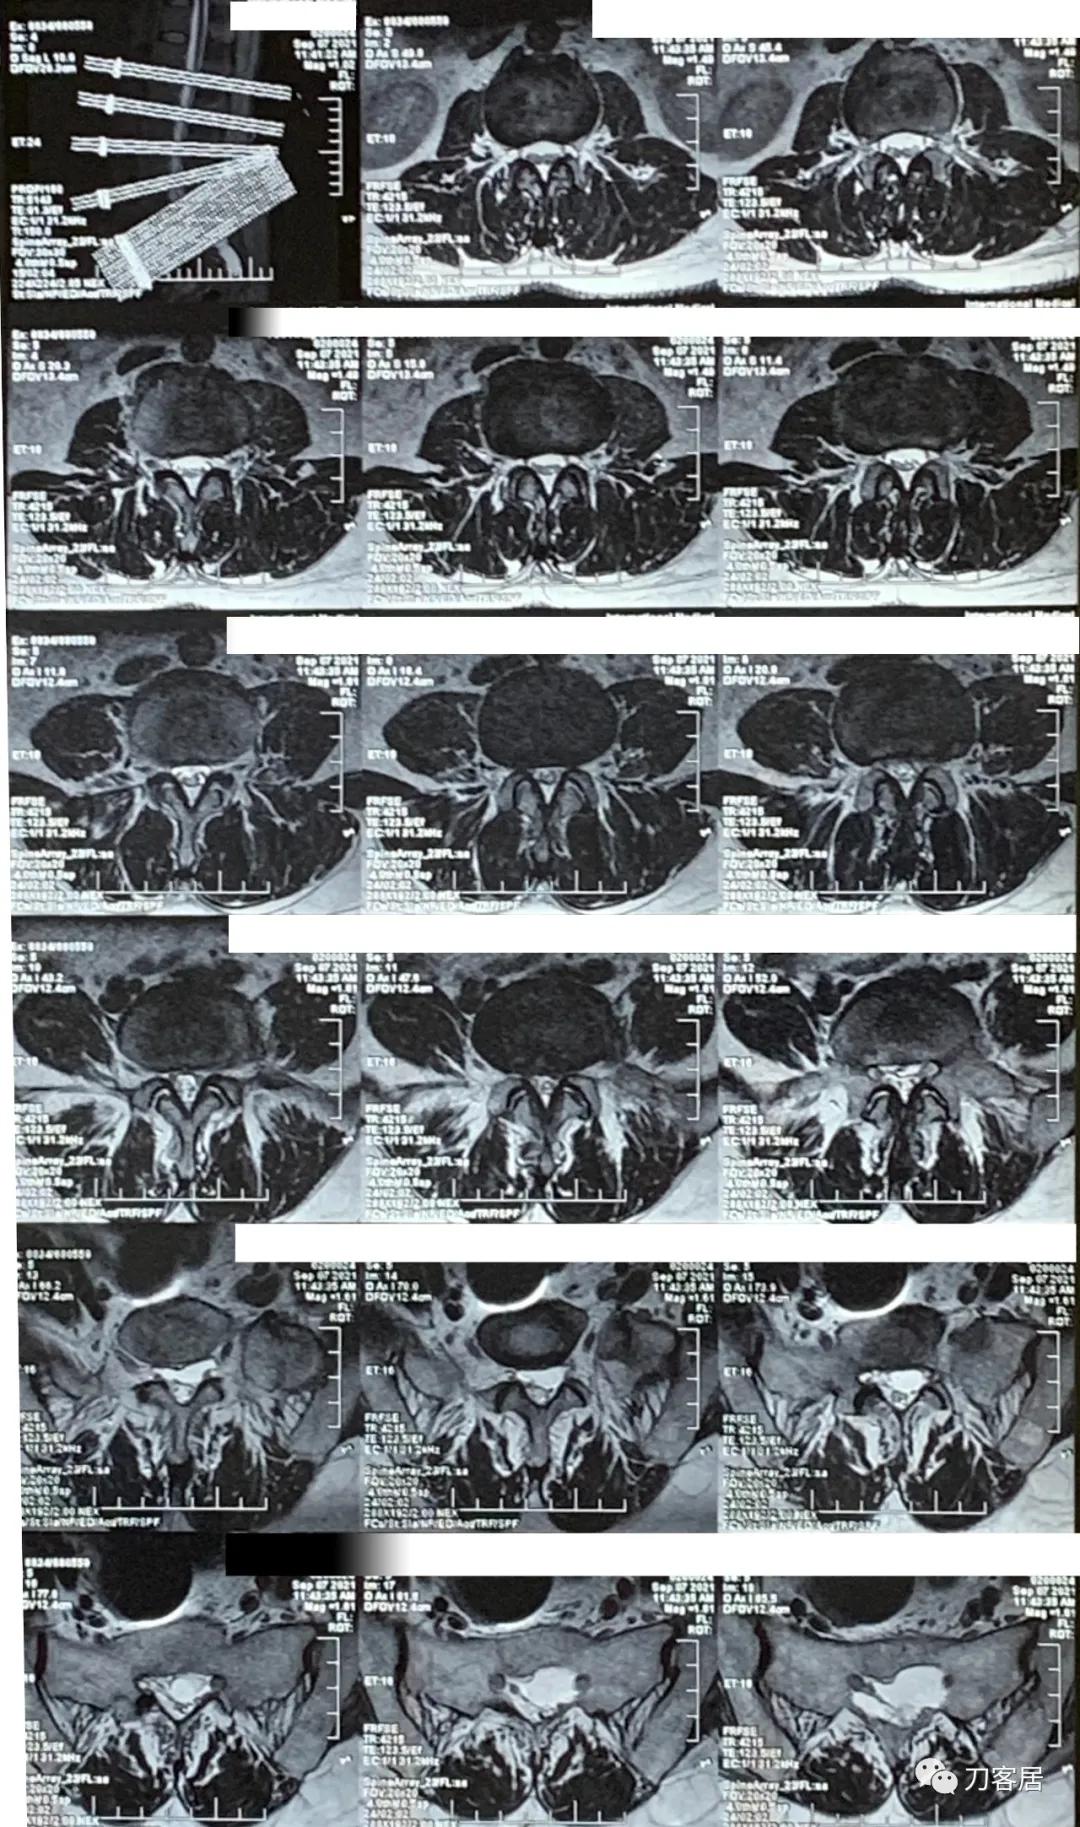

图5. 20210907西安国际医学中心腰椎MRI横截面,提示骶管囊肿较大,且宽。

图6. 20210907西安国际医学中心腰椎MRI横截面扫描,提示腰3-5椎间盘突出及椎管狭窄均不严重。